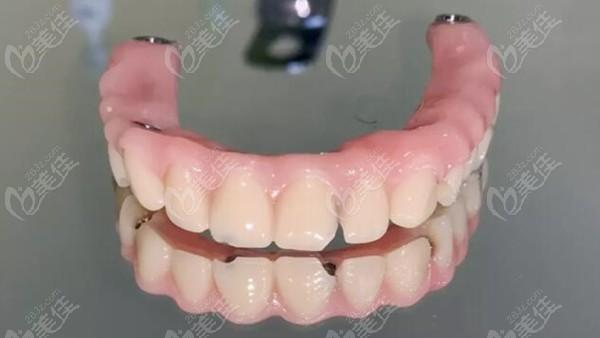

种植牙半口桥架与传统的义齿相比,美观度更高。它能够完美地融入口腔,与自然牙齿一样,形态与颜色也与周围牙齿相似,让人感觉非常自然。这种修复方式能够让缺失的牙齿得到良好的修复,让人的嘴巴焕发出新的笑容。

与其他修复方式相比,种植牙半口桥架的美观度更加突出。无论是在社交场合还是在日常生活中,它都能让人拥有自信的笑容,让人更加美丽自信。

种植牙半口桥架的形状与周围牙齿相似,非常符合人体工程学设计,能够非常好地适应口腔环境,减少对口腔软组织的压迫,让人感到非常舒适。在使用中,种植牙半口桥架的稳定性也非常好,不会产生松动或异物感,让人感到非常自然。